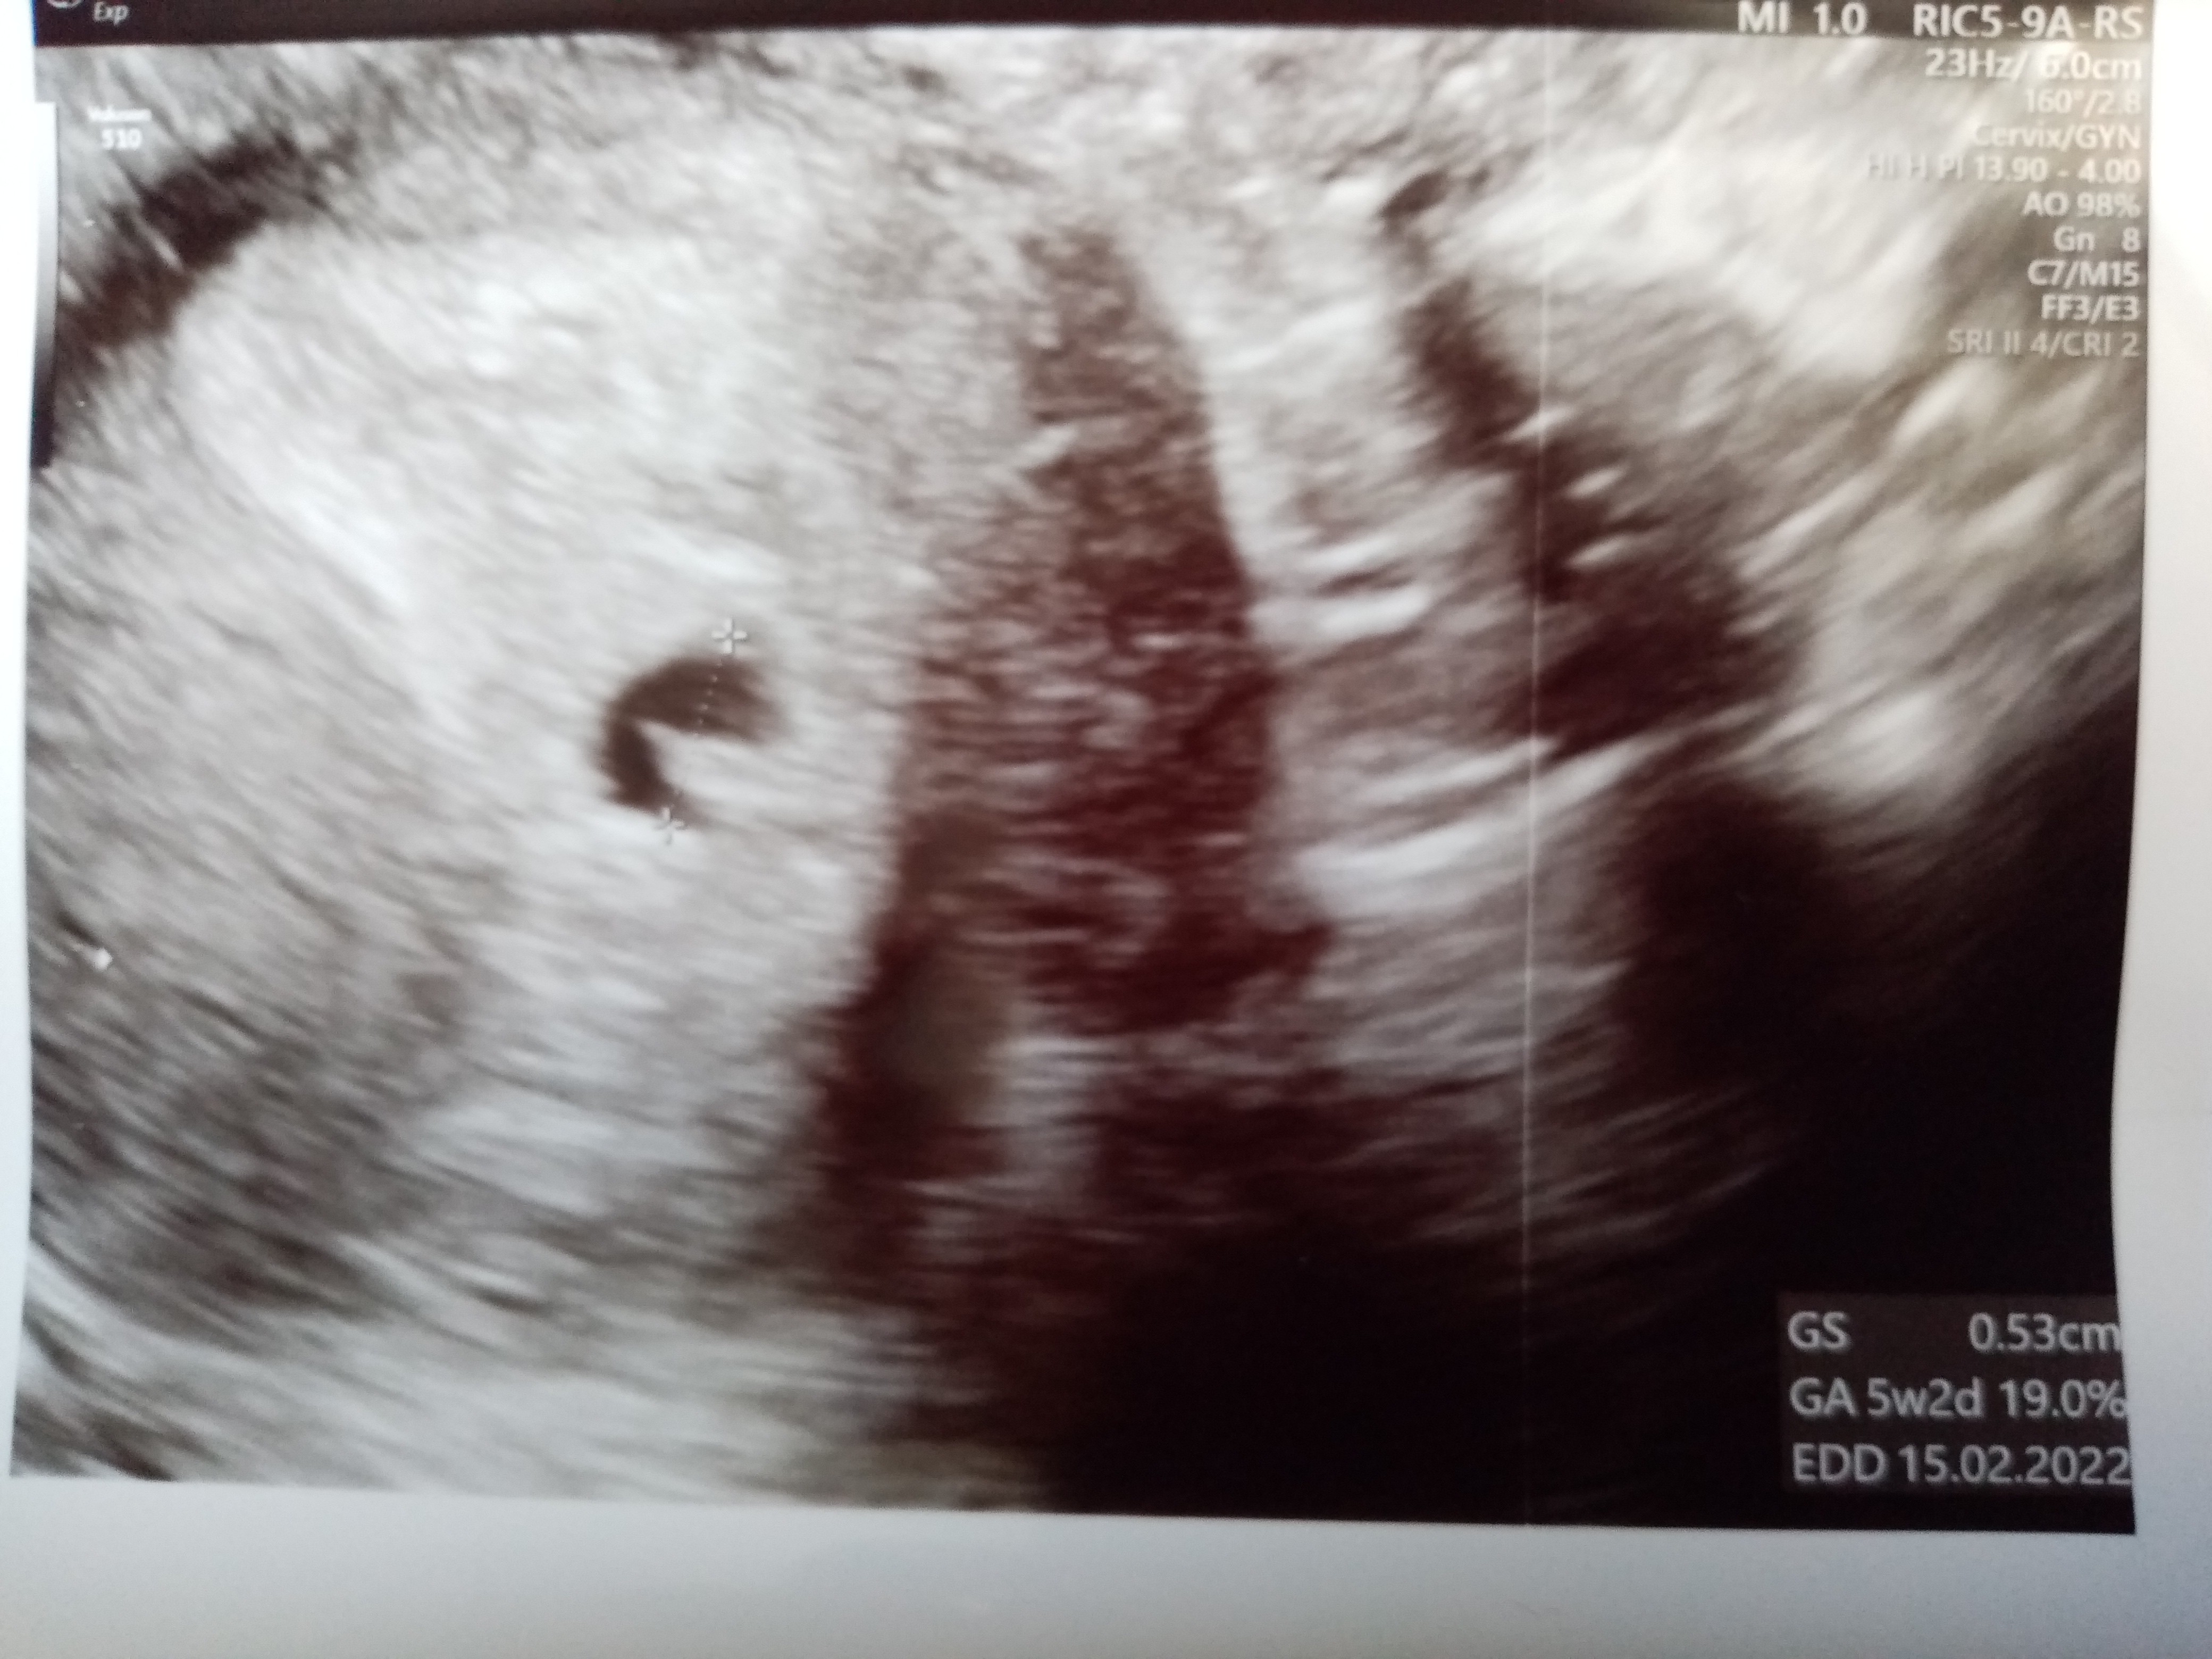

Witam się nieśmiało. Ostatnia OM 8 Mają. Dzisiaj byłam u ginekologa 5t5d i jest narazie tylko pęcherzyk 5mm ale to w środku to może być już zalążek zarodka? Jak myślicie

• IMG_20210617_172726.jpg

IMG_20210617_172726.jpg

1,6 MB · Wyświetleń: 70

Mówiła że może to być zarodek ale jeszcze bez echa serca. Dwa dni temu pęcherzyk był jeszcze bardzo malutki i bałam się że coś może być nie tak.